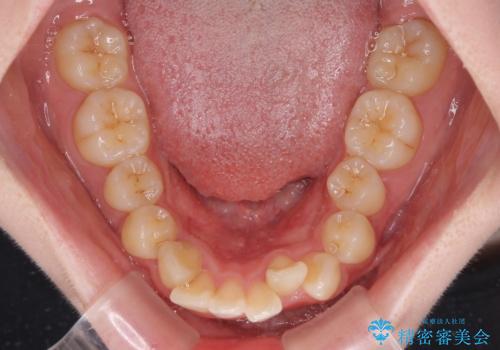

- 下顎の前歯が上顎の歯肉に咬みこむくらいに突出した上顎前歯を気にして来院された患者様です。

口元の突出感はないものの、上顎前歯が前方に傾斜して突出しており、前後に大きなズレがあり非常に深い咬み合わせとなっていました。

前突間を改善するため、上顎左右の第一小臼歯を抜歯してワイヤー装置にて矯正治療を行うこととしました。

深い咬み合わせは上顎前歯を引っ込ませる大きな障害となるため、咬み合わせの改善が非常に重要となります。やや期間はかかりましたが、当初狙った通りの仕上がりで治療を終えることができました。